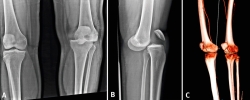

En la imagen radiográfica se apreció luxación de rodilla anteromedial (Figuras 1A y 1B).

En el quirófano, bajo sedación y relajación muscular, se redujo la luxación, inmovilizando con una férula posterior inguinopédica. Se comprobó la normalidad del estado neurovascular tras la reducción y se administró heparina profiláctica. Se solicitó una angiotomografía computarizada (angio-TC), donde se apreció que el sistema vascular era permeable en la lesión (Figura 1C). En la resonancia magnética (RM) se diagnosticó la rotura de ambos ligamentos, del cruzado anterior y del complejo posteroexterno.

Figura 1. A y B: luxación de rodilla anteromedial; C: angiotomografía computarizada.